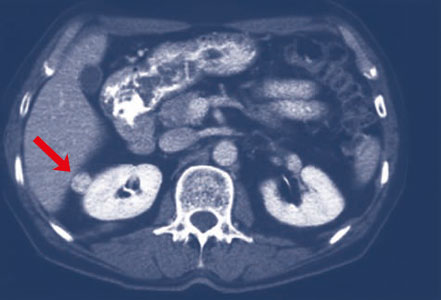

Moderne Ultraschallgeräte und Schnittbildverfahren (Computertomographie (CT) und Magnetresonanztomographie (MRT)) haben dazu geführt, dass die Nierentumoren bei Diagnose häufig noch sehr klein (< 2 cm) sind.

Kleiner Nierentumor an der rechten Seite

Pathologie des Nierentumors